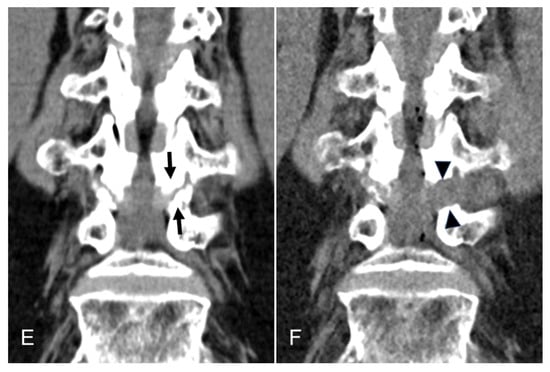

Figure 3.

An illustrative case of an 81-year-old female patient treated with TELLRD. (A) Preoperative axial CT showing central and lateral recess stenosis at the L3–L4 level (arrows). (B) Postoperative axial CT showing lateral spinal canal decompression following undercutting of the hypertrophic SAP and LF compressing the TNR (arrowheads). (C) Preoperative sagittal CT showing lateral recess stenosis at the L3–L4 level (arrows). (D) Postoperative sagittal CT showing lateral spinal canal decompression following undercutting of the hypertrophic SAP and LF compressing the TNR (arrowheads). (E) Postoperative coronal CT showing lateral recess stenosis at the L3–L4 level (arrows). (F) Postoperative coronal CT showing lateral spinal canal decompression following undercutting the SAP and LF compressing the TNR (arrowheads). TELLRD, transforaminal endoscopic lumbar lateral recess decompression; SAP, superior articular process; LF, ligamentum flavum; TNR, traversing nerve root.